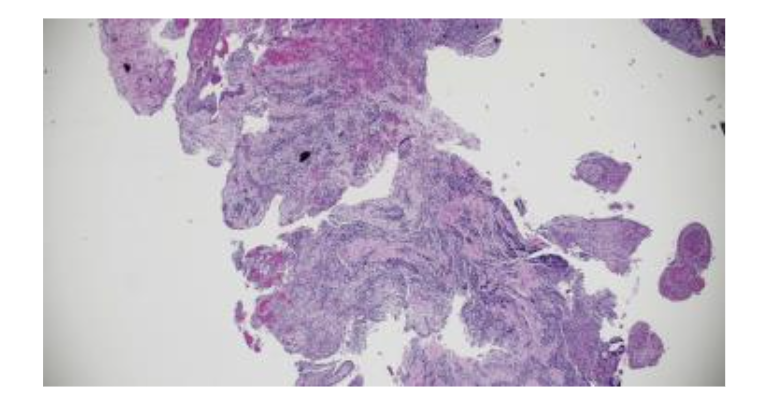

Figure 6. Histopathology confirmed a Radicular Cyst (K04.8), ruling out malignancy. Pathologist reported H&E-stained soft tissue section consists of loose fibrovascular connective tissue containing a mixed but predominantly chronic inflammatory infiltrate associated with nests and anastomosing cords of mildly hyperplastic stratified squamous epithelium.